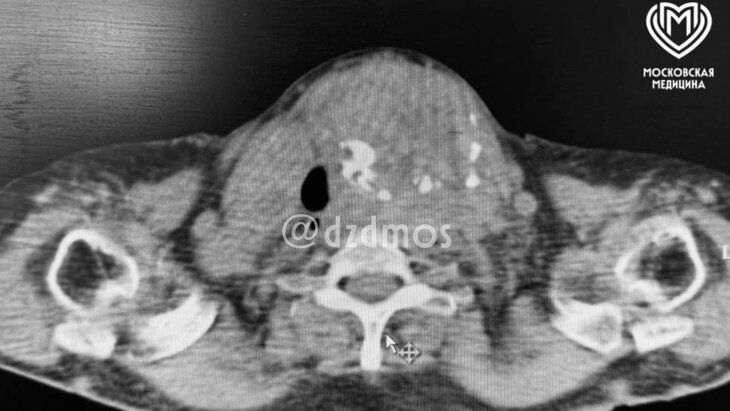

Фото: телеграм-канал "Московская медицина"

Врачи ГКБ № 24 в столице спасли 79-летнюю пациентку с огромным зобом, сообщает телеграм-канал московского Депздрава.

Зоб размером практически с волейбольный мяч сжимал трахею, оставляя в ней всего 4 миллиметра свободного пространства. В крови женщины уже накопилось много углекислого газа (в три раза больше нормы).